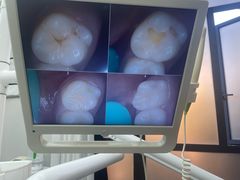

• 牙博士口腔品牌连锁(杨浦店)

• -牙博士口腔品牌连锁(杨浦店)